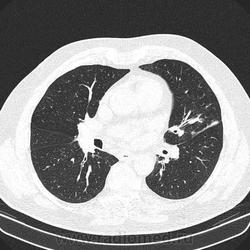

Альвеолярное кровоизлияние.

хорошо бы с контрастом посмотреть. подозрений клинически на ТЭЛА не было?

Полисегментарная пневмония.

оказалось ТЭЛА.

эту пневмонию вылечили, через некоторое время пациент поступил с подобной картиной в другом легком.

потом нашли тромб в артериях н/конечностей.